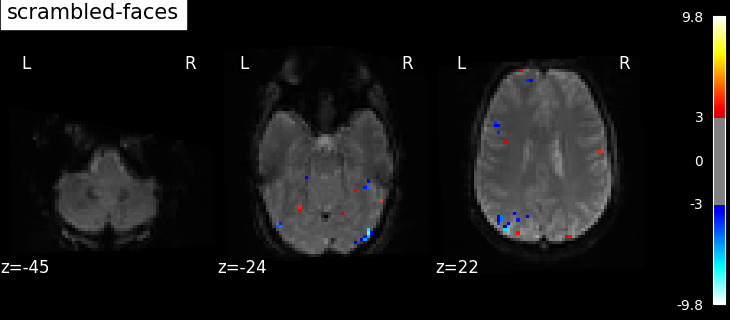

Now we can compute contrast-related statistical maps (in z-scale), and plot them.

for contrast_id, contrast_val in contrasts.items():

z_map = fmri_glm.compute_contrast(contrast_val, output_type="z_score")

plotting.plot_stat_map(

z_map,

bg_img=mean_image,

threshold=3.0,

display_mode="z",

cut_coords=3,

black_bg=True,

title=contrast_id,

)

contrast id: scrambled-faces

Based on the resulting maps we observe that the analysis results in wide activity for the ‘effects of interest’ contrast, showing the implications of large portions of the visual cortex in the conditions. By contrast, the differential effect between “faces” and “scrambled” involves sparser, more anterior and lateral regions. It also displays some responses in the frontal lobe.